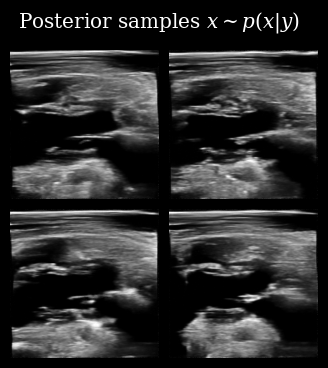

That looks correct, we now proceed with posterior sampling to generate some samples from the Bayesian posterior \(\{\mathbf{x}_t^{(i)}\}_{i=0}^{N_p} \sim p(X_t \mid \mathbf{y}_{<t})\).

[11]:

posterior_samples = diffusion_model.posterior_sample(

measurements=measurement_buffer,

mask=mask_buffer,

n_samples=n_particles,

n_steps=n_posterior_steps,

initial_step=0,

omega=10,

)

animate_samples(

posterior_samples[0],  # posterior samples has an extra batch dim of length measurements

"./task_based_posterior_samples.gif",

title=r"Posterior samples $x\sim p(x | y)$",

fps=9,

zea: Successfully saved GIF to -> task_based_posterior_samples.gif

Task Based Posterior Samples